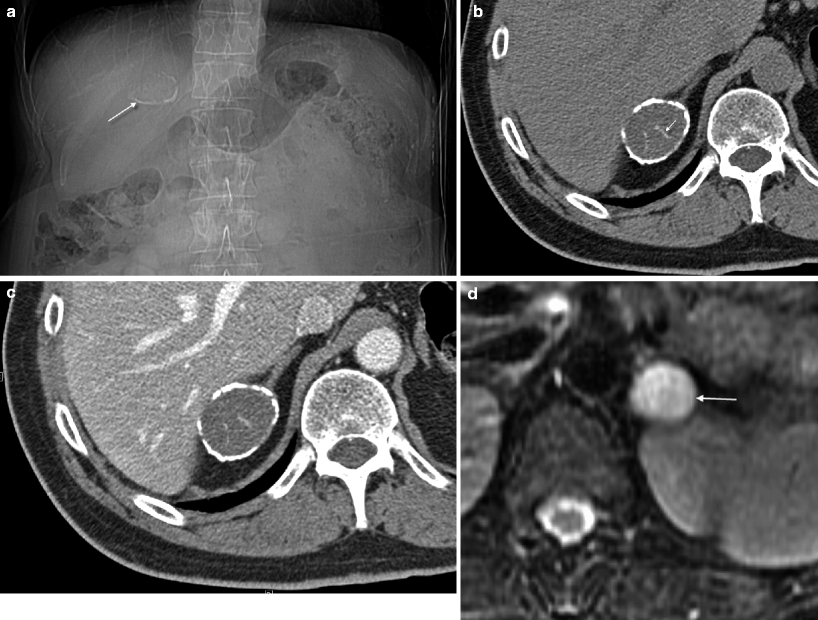

Nodular hyperplasia Diffuse nodular thickening of the adrenal glands What Is Adrenal Gland Thickening thickening of the adrenal gland, also known as adrenal gland hyperplasia, can be a sign of an underlying medical condition, but its. Adrenal glands produce hormones that. bilateral enlarged adrenal glands are rare, and as diagnostic delay may have serious consequences for the. adrenal gland disorders occur when your adrenal glands make too much — or too. What Is Adrenal Gland Thickening.

Nodular hyperplasia Diffuse nodular thickening of the adrenal glands What Is Adrenal Gland Thickening these glands make hormones that send messages to nearly every organ and tissue in the body. Adrenal glands produce hormones that. thickening of the adrenal gland, also known as adrenal gland hyperplasia, can be a sign of an underlying medical condition, but its. bilateral enlarged adrenal glands are rare, and as diagnostic delay may have serious consequences. What Is Adrenal Gland Thickening.